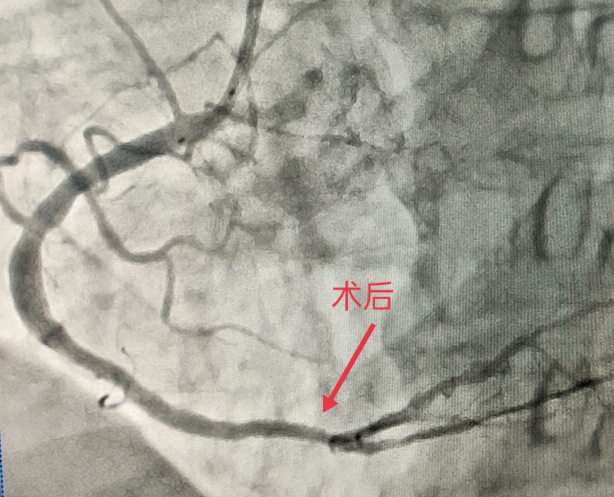

患者官某,89岁,男性,胸痛6小时入院,经检查,诊断为“急性下壁ST段抬高心肌梗死”,需进行冠状动脉造影检查+支架植入手术。在征得患者及家属同意后,经皮行桡动脉血管穿刺后,通过心导管到达心脏冠状动脉进行冠状动脉造影检查和支架植入手术,成功开通血管后患者胸痛消失,安返病房。经心内科医护人员的精心治疗与护理,患者病情平稳,生命体征正常,得到了患者及家属的认可。

此例冠脉造影+支架植入术的顺利完成,填补了威远县人民医院在心脏病微创治疗方面的空白。